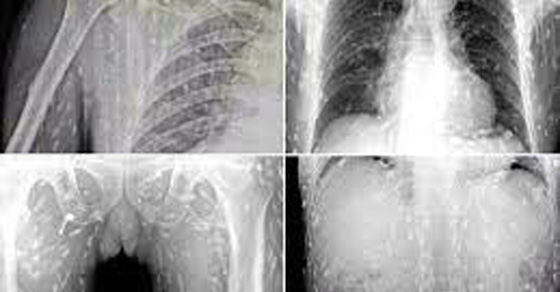

Một người đàn ông Trung Quốc, cũng vì đam mê với các món sushi mà đã để toàn bộ cơ thể của mình tràn ngập những con giun ký sinh. Người đàn ông đã đến tham vấn bác sĩ của mình về một cơn đau bụng dữ dội và ngứa da. Sau khi quét toàn bộ cơ thể, bác sĩ tiết lộ nguyên nhân kinh hoàng - toàn bộ cơ thể của anh ta chứa đầy giun.

Một loài sán dây gọi là Diphyllobothrium sống kí sinh tất cả các loại cá. Đây là loài kí sinh trùng gây ra một căn bệnh được biết đến dưới tên Diphyllobothriasis và nó thường xảy ra khi tiêu thụ cá chưa nấu chín hoặc sống. Các triệu chứng đáng chú ý đầu tiên bao gồm tiêu chảy, đau bụng, giảm cân và yếu.Tất nhiên, bệnh có thể gây tử vong nếu giun chui vào não. Khi đi vào cơ thể, giun bắt đầu phát triển và có thể tồn tại trong cơ thể trong nhiều năm.Thực tế là loại giun có thể ở trong cơ thể vài tuần hoặc thậm chí vài tháng mà không thể phát hiện.

Nhiều nghiên cứu đã chỉ ra rằng việc tiêu thụ cá chưa nấu chín hoặc sống thường có thể gây ra nhiễm các loại ký sinh trùng khác nhau và một số các nghiên cứu cho thấy đôi khi thậm chí cá nấu chín cũng có thể gây ra nhiễm ký sinh trùng.